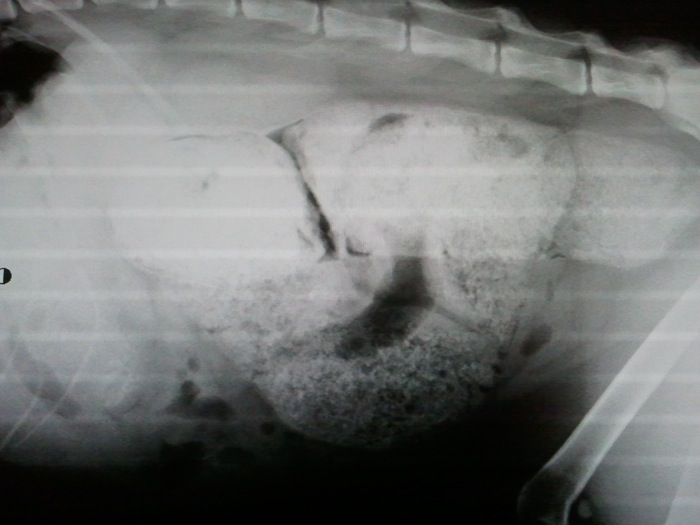

| Pruebas | Radiografías donde se aprecian retenciones de heces periódicas. |

En la imagen en el cuadrante inferior derecho se aprecia el ciego y continúa hacia la izquierda con el colon tan distendido, a pesar de estar vacío, que parece más un estómago.